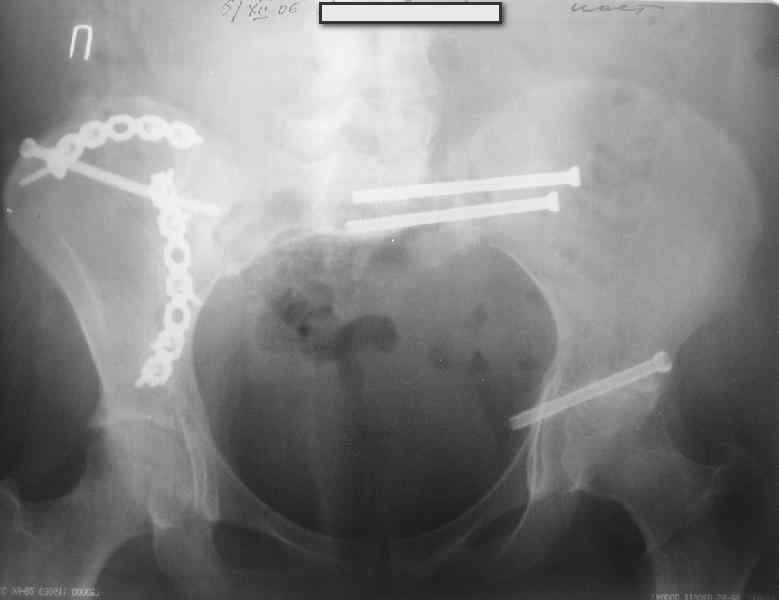

Здравствуйте, коллеги. Какие будут мнения по поводу лечения представляемой больной?

Молодая девушка 19 лет, травма 1 год назад, тогда же прооперирована.

В настоящее время имеются ноющие боли в области крестца слева, нарушение походки, ощущение неуверенности, слабости в левой нижней конечности, неврологически -непостоянные парестезии в левой нижней конечности. Ходит с дополнительной опорой, страдает от ожирения.

В приложении снимки при поступлении и послеоперационные год назад.

Могу сказать одно: миграция винтов и нестабильность синтеза левого подвздошно-крестцовогоо сочленения очевидна.